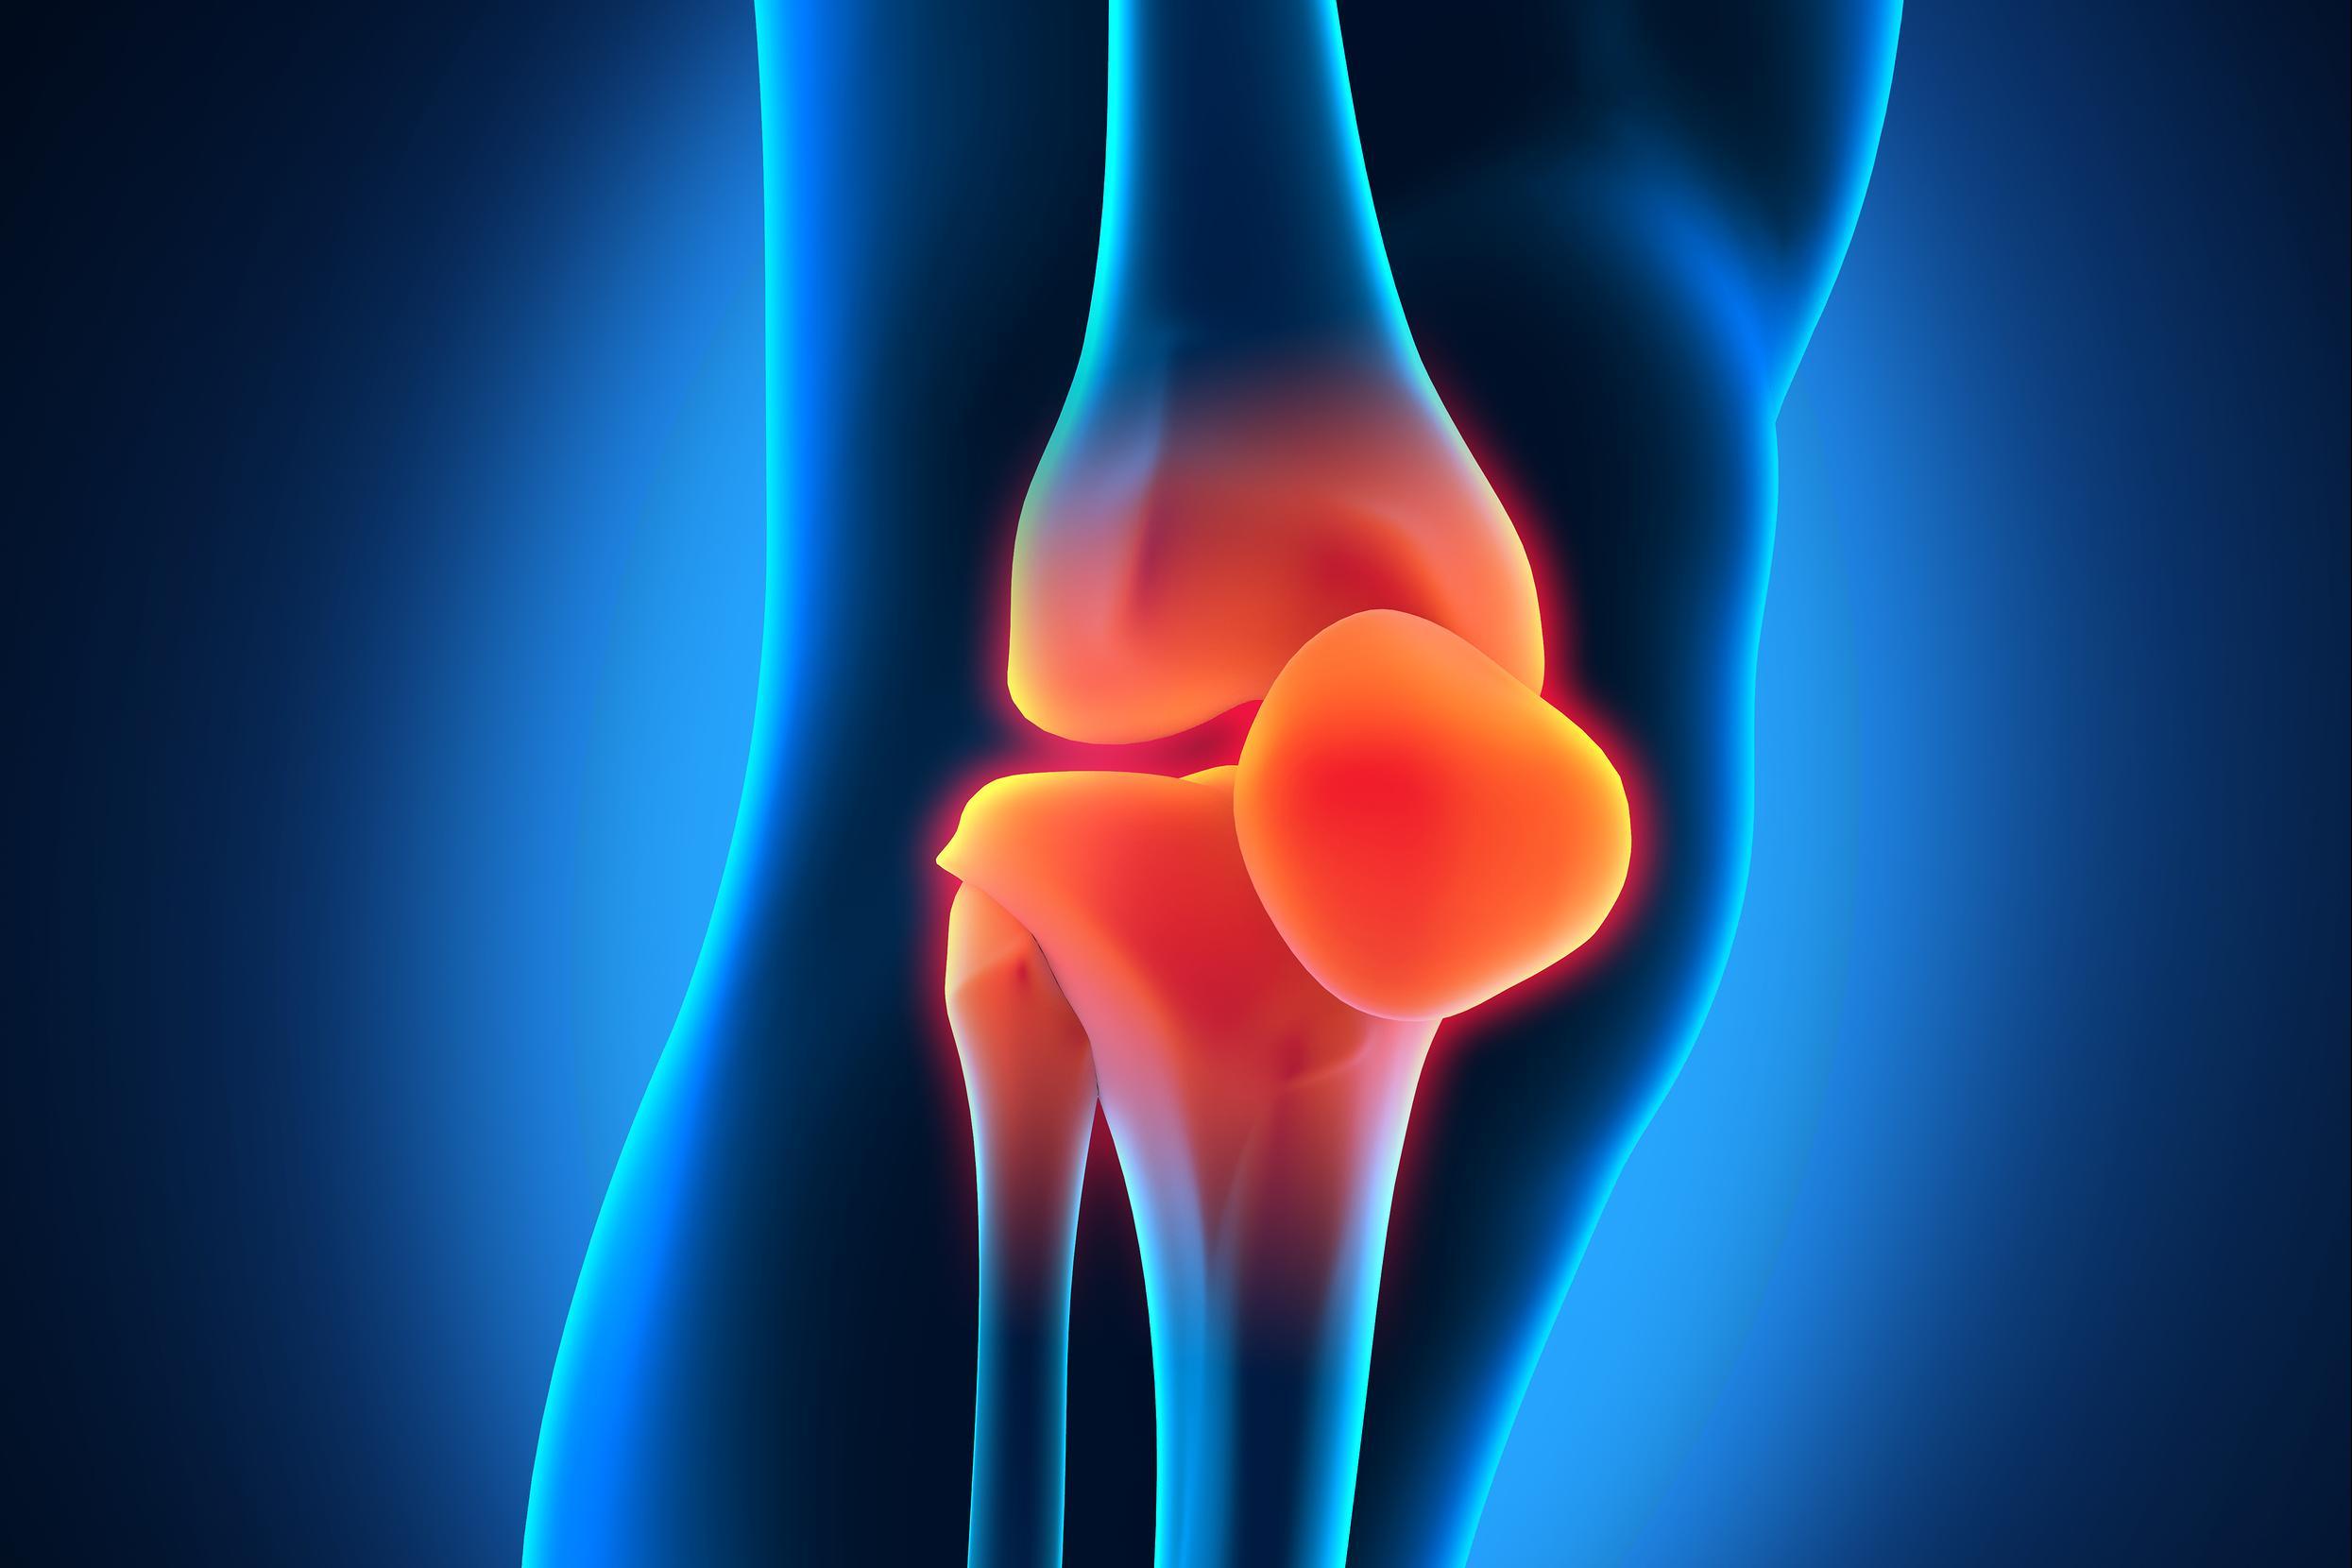

Прежде всего, дегенеративные изменения и износ суставов возникают у людей пожилого возраста. Они возникают вследствие износа хрящевой ткани, уменьшения выделения синовиальной жидкости и чаще всего поражают наиболее нагруженные суставы — бедра, колени, локти.

Так возникает артроз коленного и тазобедренного суставов, который чаще всего приводит человека к инвалидности.

Чтобы определить, в какой стадии заболевания находится сустав, делают рентген или МРТ. По снимкам можно увидеть, как уменьшается высота щели между костями сустава, и разрастаются шипы (остеофиты). На последней третьей стадии щель может исчезнуть совсем, и кости срастаются. Такая деформация сустава является необратимой. Чтобы обеспечить подвижность сустава и дать человеку возможность полноценно жить, делают эндопротезирование, если отсутствуют противопоказания.